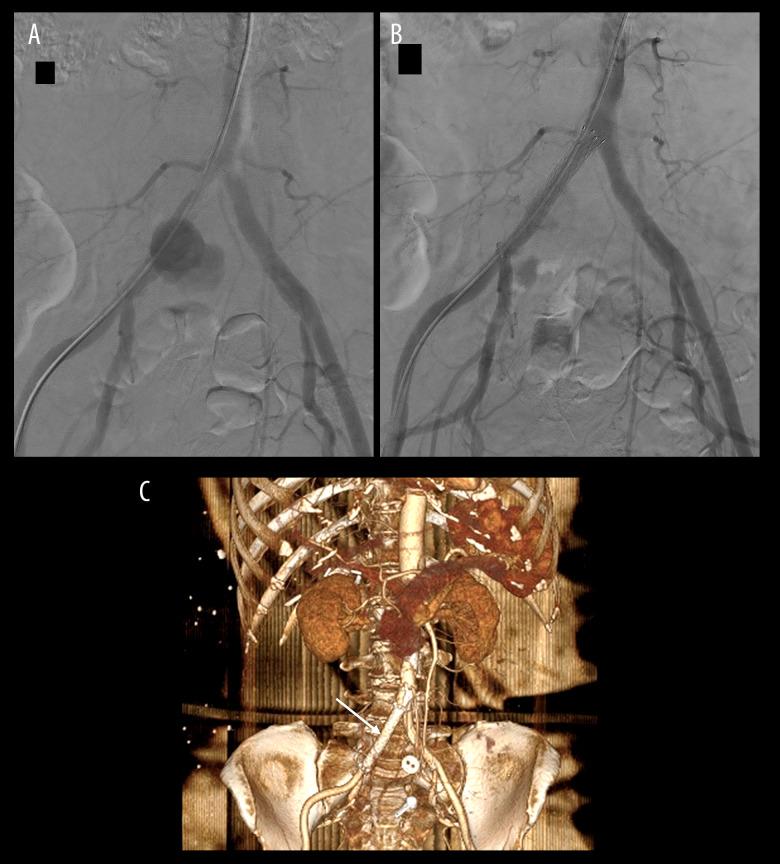

Acute iliac artery rupture: endovascular treatment.

Cardiovasc Intervent Radiol. 2007 Mar-Apr;30(2):281-5. doi: 10.1007/s00270-005-0357-9.